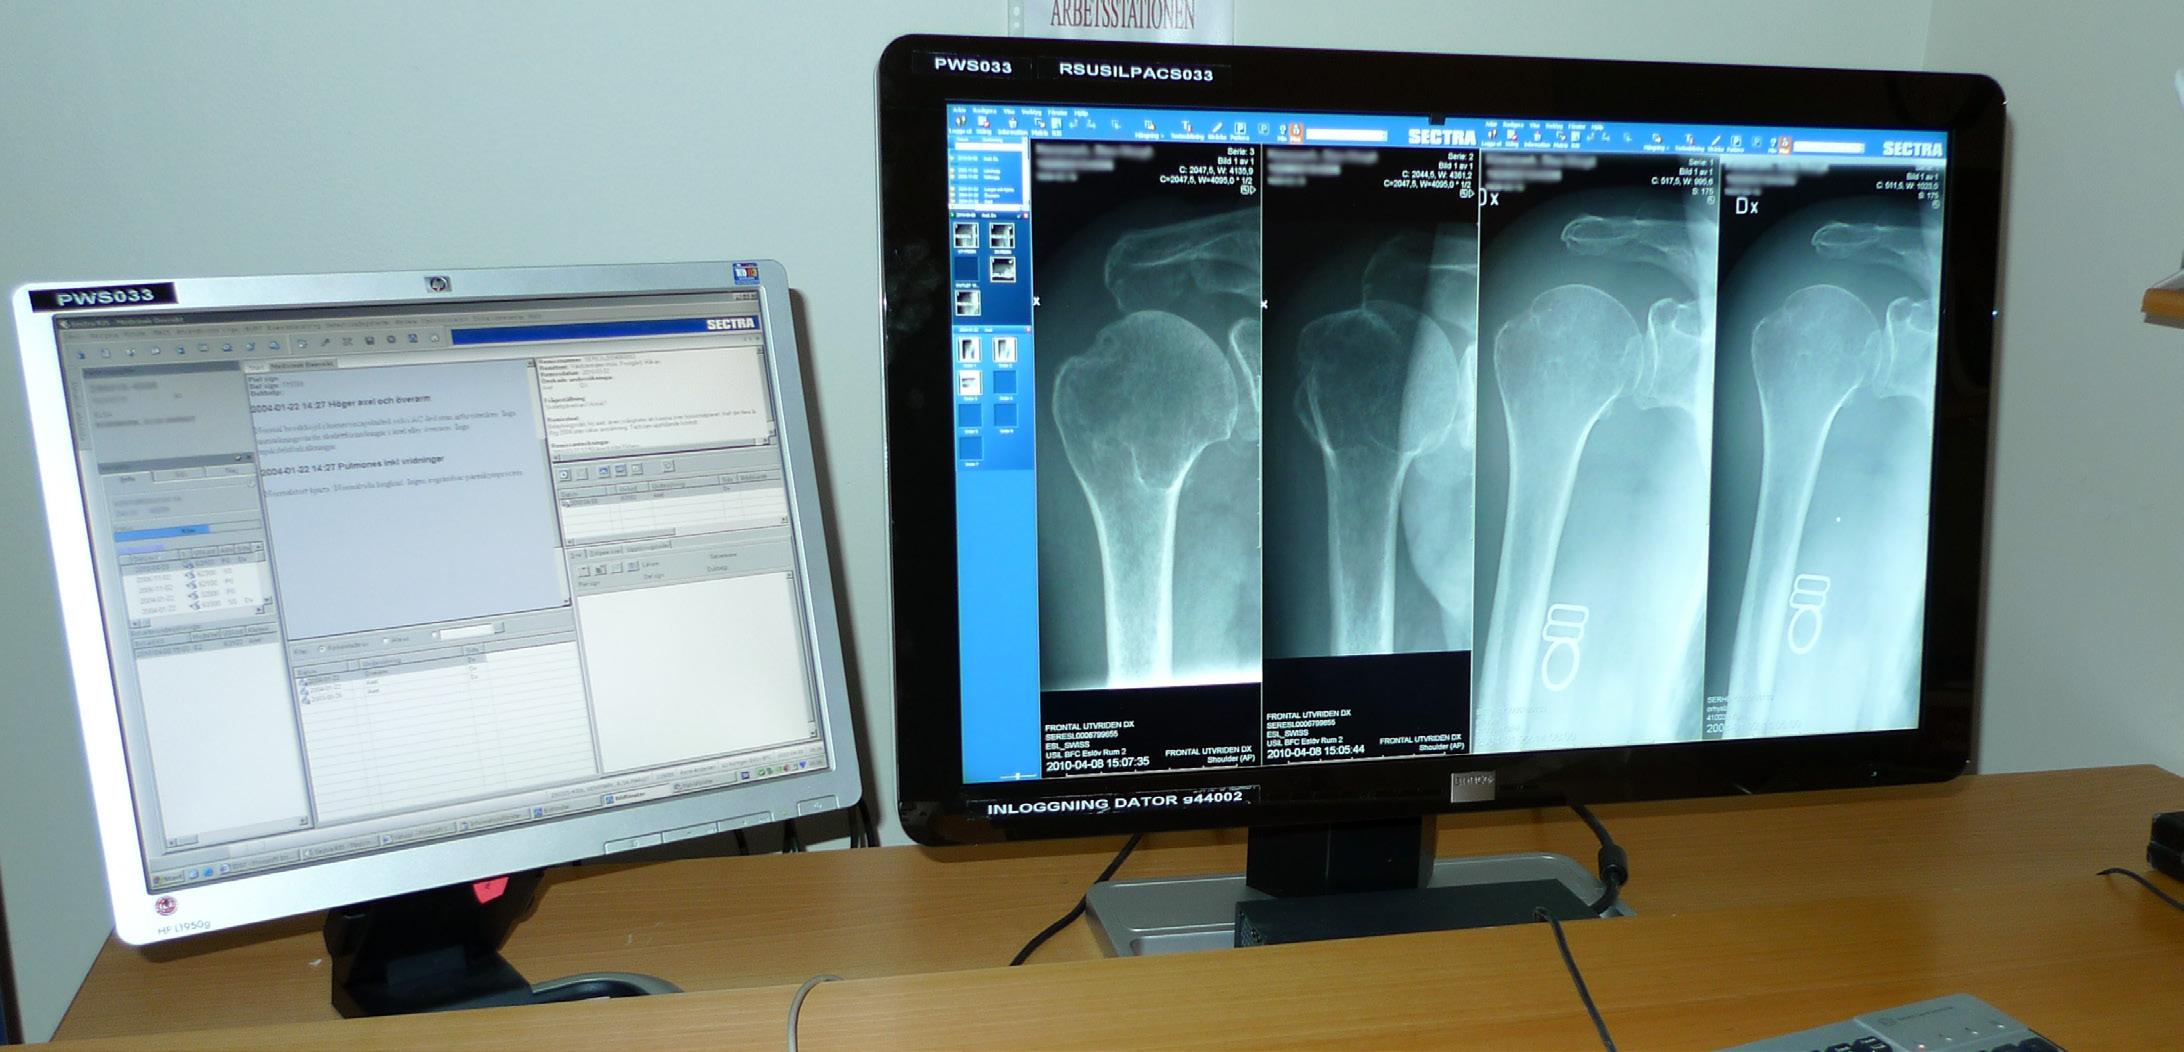

Förutsättningen för att kunna göra bilder i flera plan och 3D-rekonstruktioner kom i och med den digitala revolutionen kring millennieskiftet då RIS och PACS snabbt introducerades över landet. Bild 2. Mycket av utvecklingen leddes av det svenska företaget Sectra som idag har ungefär hälften av den svenska marknaden. Eftersom CT-detektorerna ger bilder som är 0,625 mm tunna och detektorraderna innehåller fler än 1000 detektorer blir

Bild 1. Den första skalldatortomografen från EMI. Foto Mats Geijer i Deutsches Röntgenmuseum, Remscheid-Lennep. Bild 2. Patient med scapulafraktur. I ett modernt PACS kan patologin demonstreras i tre invinklade plan samt 3D-rekonstruktion samtidigt.